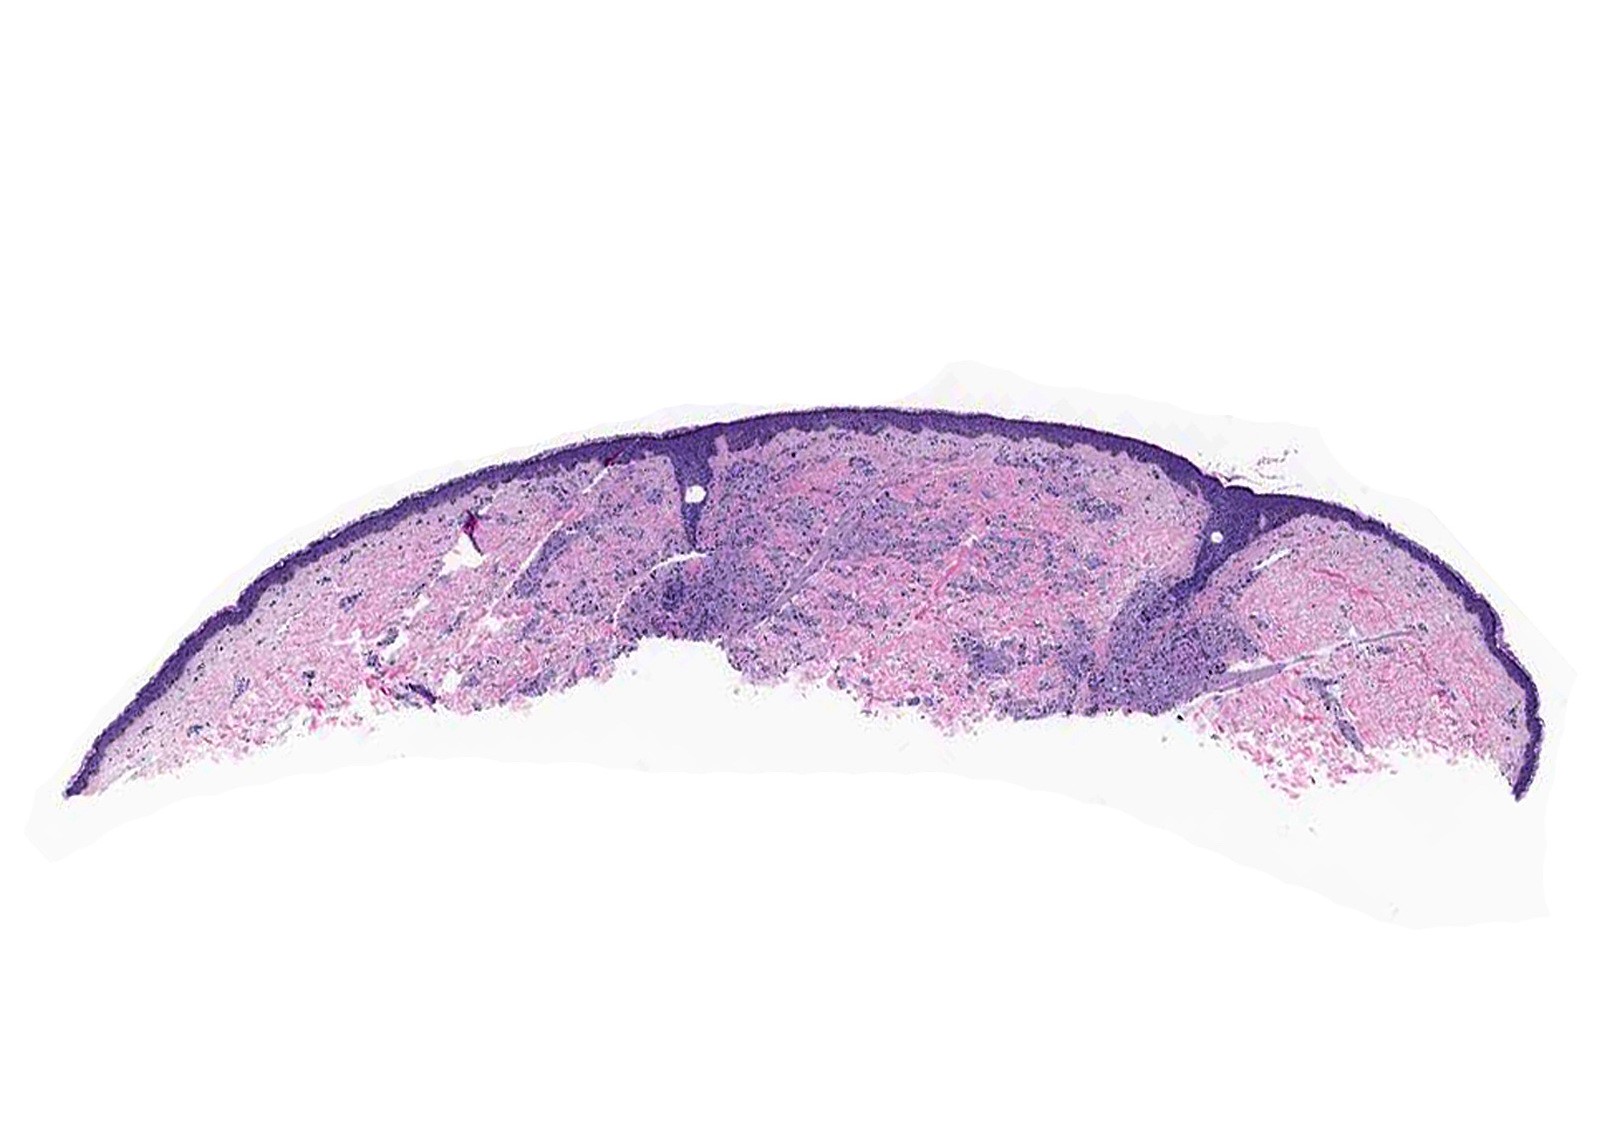

Microscopic (histologic) description

- Infiltrative or circumscribed architecture

- Can involve the subcutis

- Epidermis can show pseudocarcinomatous hyperplasia

Microscopic (histologic) images

Contributed by Jarish Cohen, M.D., Ph.D.